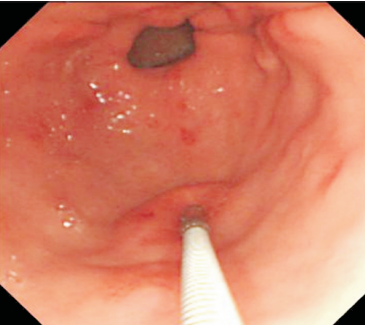

Figura 2 a 7. Etapas da biópsia assistida por incisão de mucosa. Fig. 2. Localização da lesão utilizando gastroscópio convencional com cap.Fig. 3 e 4. Incisão na região central da lesão sob auxílio de needle-knife.Fig. 3 e 4. Incisão na região central da lesão sob auxílio de needle-knife.Fig. 5. Divulsão das camadas com pinça de biópsia.Fig. 6. Exposição da submucosa e da cápsula da lesão (seta verde).Fig. 21. Biópsias da lesão sob visão direta. Nota: Posteriormente, realizou-se incisão da cápsula da lesão para biópsia adicionais e, ao término, colocação de clipes para o fechamento do sítio manipulado. Fonte: arquivos do Instituto do Câncer do Estado de São Paulo (ICESP/HCFMUSP).